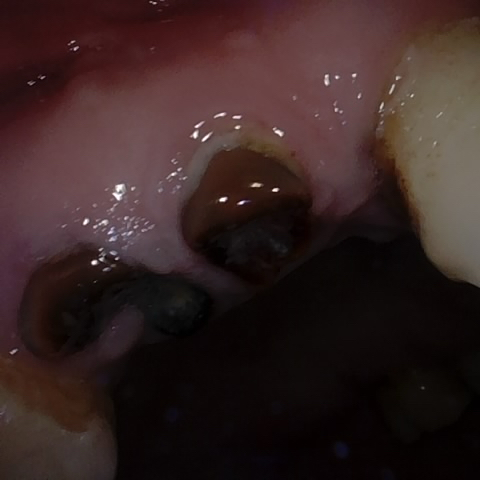

Incorrect Quality Level

The reference annotation for this image is

None

.

Please select the correct quality level.

Annotated as "Good"